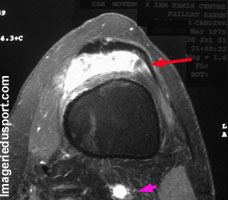

L'Hémangiome Synovial est une tumeur rare, quasiment toujours retrouvée au niveau du genou (60%) ou au niveau du coude (30%).

- intra-articulaire : 67 %, érosions osseuses (parfois érosions étendues, zones de réflexion synoviale). Présence trés inconstante de phlébolites.

- synovite villo-nodulaire, notamment en présence de dépôts d'hémosidérine en IRM